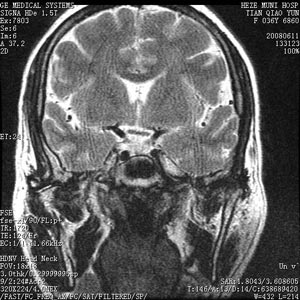

垂體前葉機能減退症(席漢氏綜合症)

垂體前葉機能減退症(西蒙-席漢綜合徵)是多種病因所致腺垂體激素分泌不足,繼發性腺、甲狀腺、腎上腺皮質功能低下所呈現的臨床征群。. 病因 垂體瘤...、智力減退、動作遲緩、食慾減退、畏寒、少汗、皮膚乾燥、面部虛腫蒼黃、甚至...

Sheehan綜合徵

。疾病描述這是一百多年前由席漢氏(Sheehan)發現的一種綜合症,當產後...,乏力,脫髮,畏寒,閉經,乳房萎縮等,嚴重者可致死。臨床上稱之為席漢氏綜合症。 腦下垂體前葉分泌很多促激素,如促性腺激素,促甲狀腺素,促...